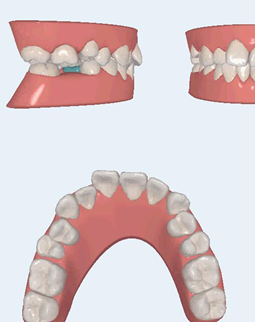

拿到牙套了,其实还有点怀疑,就这两个塑料的东西,真的可以让我的牙齿矫正吗,何况我还有个缺牙的间隙,看了墙上很多顾客和医生的合影还一墙的牙套盒,20多副的有,3、4十副的也有,很多人选择应该没错的!医生说根据个人情况有不一样的方案,我的是42副,隔断时间换一副,牙齿变齐了牙套也要跟着变化的!医生还给我演示了3D的动画,居然这么的高科技!另外医生提醒我注意刷牙卫生,还有一些注意事项,原来牙套戴在牙上是有感觉的,还真的看不出来,隐形的贵也有道理的哈O(∩_∩)O